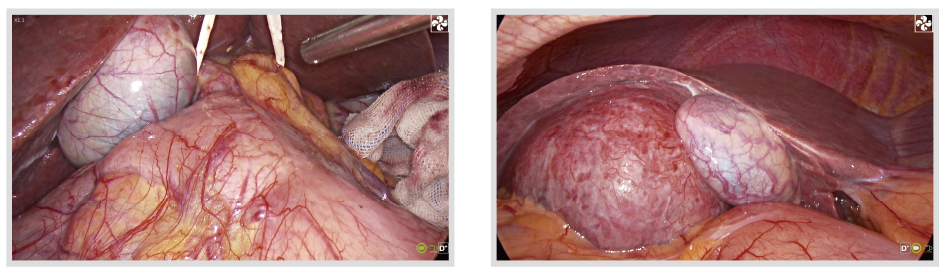

THORACIC SURGERY

Optimized Algorithm to Reveal More Details and Provide Clear Image

Drive unique optimization algorithms through intelligent analysis to efficiently optimize image's clarity, color, contrast, and details.